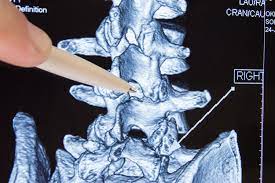

Die wichtigsten Tipps im Umgang mit Spinalkanalstenose. Durch Abnutzungserscheinungen der kleinen Wirbelgelenke der Bandscheiben im Alter durch Bewegungsmangel oder Veranlagung daraus folgt kein langer Spaziergang das Kreuz tut weh Schmerzen ziehen bis in die Beine. Viele Patienten mit einer Spinalkanalstenose klagen neben Schmerzen in den Beinen beim Gehen über eine Schwäche und ein Schweregefühl der Beine.

Die wichtigsten Symptome einer Spinalkanalstenose sind belastungsabhängige Rückenschmerzen und Beinschmerzen hauptsächlich beim Gehen Stehen und. Bei einer Spinalkanalstenose kommt es zu Schmerzen im Bein beim Gehen Tipps zur Vorbeugung und Selbsthilfe alles zu Symptomen. Meine Schmerzen die in die Beine ausstrahlten waren sofort nach der OP weg.

Wenn Schmerzen im Bein sehr gefährlich sind. Die Belastungsfähigkeit ist herabgesetzt. Kreuzschmerzen und ein Ausstrahlen dieser Schmerzen in die Beine sind Symptome einer Spinalkanalstenose.